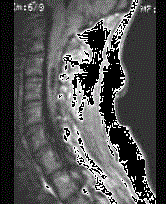

问题 某女58岁,肢体活动不灵、吞咽困难2年。查体有腱反射亢进。MRI如图示最可能的疾病为 ( )

选项 A、脑积水 B、颅底凹陷症 C、颅内肿瘤 D、小脑扁桃体下疝畸形 E、椎管内肿瘤

答案 D